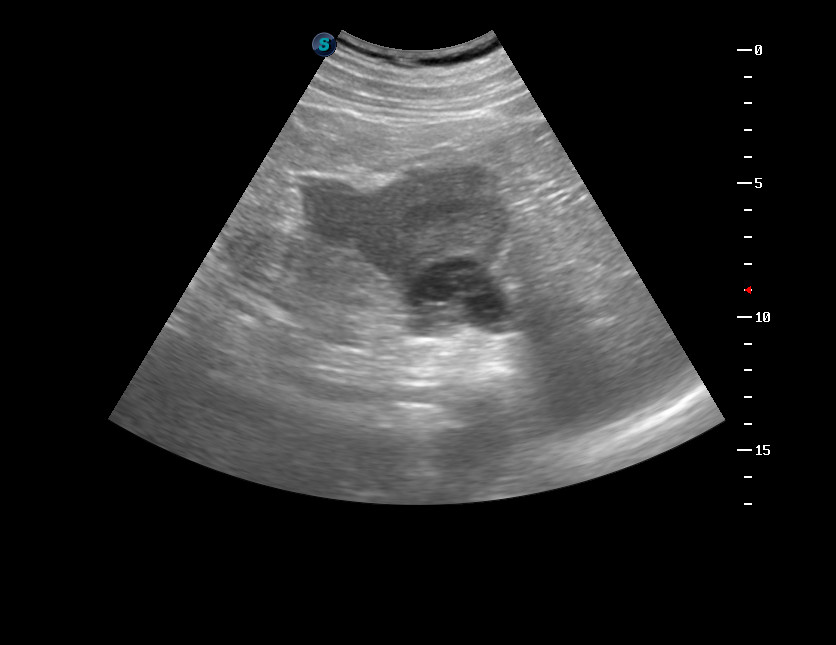

Мужчина 50 лет, жалоб не предъявляет.

В нижнем полюсе левой почки обнаружена киста с солидным внутренним компонентом. Предположена опухоль в кисте.

КТ - киста Bosniak III.

Выполнена резекция опухоли.

Гистологически - светлоклеточная карцинома.